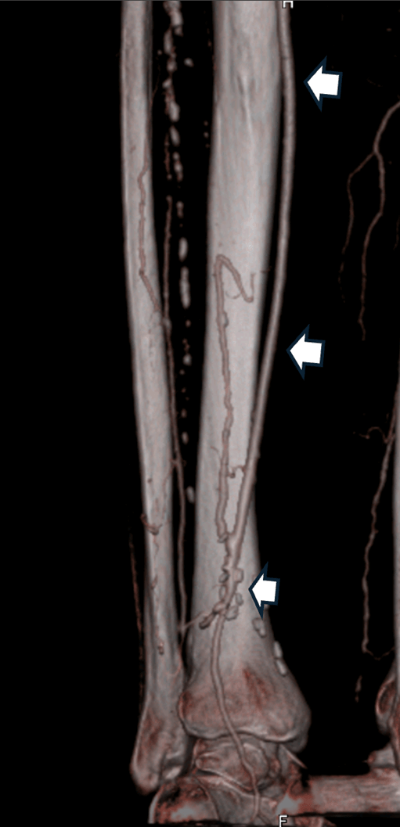

- Bypass surgery: A graft (either the patient’s own vein or a synthetic conduit) is used to divert blood flow around the obstruction (Fig. 2)

Fig. 2: Distal bypass at the ankle level using the patient’s own saphenous vein (white arrows).